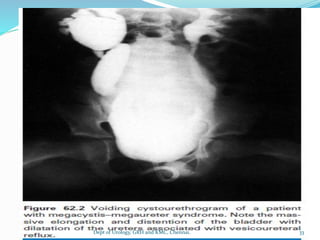

2.MEGACYSTIS:

-means large bladder

-occurs in infant and children

-common cause congenital BOO

(post.urethral valve)due to areflexia due to

spinal dysraphism

-accompany Prun belly syndrome

-occurs in diabetes insipidus which

produce large volume of urine

a.Congenital megacystis:

-congenitally huge unobstructed bladder

-large residual volume

-Trt: reduction cystoplasty 32

b.Megaureter Megacystis

syndrome:(Inner williams syndrome)

large smooth bladder with a

Trigone, dilated ureteral orifice and grossly

dilated ureter

when voids bladder empty completely

large volume refluxes into ureter when

voiding

when voiding ceases, ureter

contracts,urine rapidlly fills the bladder

bladder always distended forming

decompensated ,dilated and thin walled

34